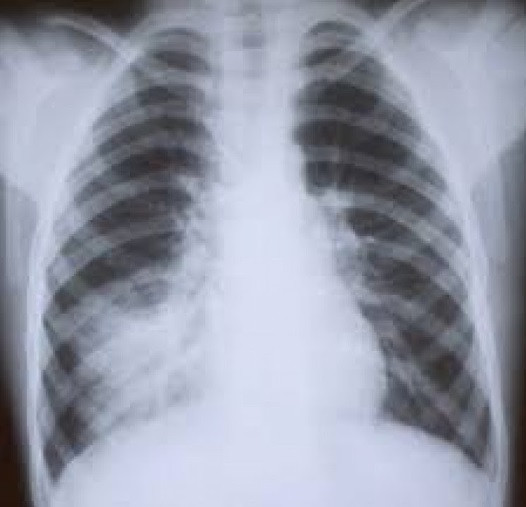

Кажете на специалиста ясно за вашите симптоми. Не се тревожете, ако не ви бъде поставена веднага диагноза, тъй като пневмонията може да бъде потвърдена само след флуорография. Когато болестта бъде открита, ще ви бъде предписано необходимото лечение. Бъдете подготвени, че след възстановяване ще трябва да преминете курс на физиотерапия и да направите физическа терапия./zdrave.to